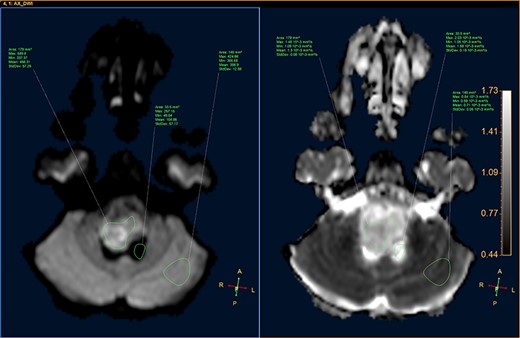

A 3-year-old male, who suffered from a sudden, tonic–clonic seizure, followed by a short period of unconsciousness, was instantly transported to Children’s Hospital 2. The patient’s medical history was normal. No neurological deficits were detected during the clinical assessment, and laboratory tests and electroencephalography were within acceptable ranges. The clinician performed a brain magnetic resonance imaging (MRI) scan, with contrast agent. No lesions were recognized in the supratentorial structures. A clear boundary cystic mass (27 × 25 × 26 mm3) was located in the medulla oblongata, without perilesional vasogenic edema. Hydrocephalus was not observed. The signal intensity of the mass was low on the sagittal T1-weighted image (Fig. 1) and high on the axial T2-weighted image (Fig. 2). On coronal fluid-attenuated inversion recovery imaging, the mass was isointense relative to the parenchyma, but the intensity was higher than that of cerebrospinal fluid (CSF, Fig. 3). On susceptibility-weighted imaging, no indicators of hemorrhage or ossification were observed within the mass. The mass was partially hyperintense on diffusion-weighted imaging (DWI) and slightly hypointense on the apparent diffusion coefficient (ADC) map. The mean ADC values of the parenchyma, mass and CSF were 0.71, 1.3 and 1.59 × 10−3 mm2/s, respectively (Fig. 4). On T1-weighted imaging, with contrast enhancement, the thin wall of the mass was very slightly enhanced, and we observed a tiny nodule inside the mass that was strongly enhanced (Fig. 5). With a provisional diagnosis of pilocytic astrocytoma, the patient underwent surgery to completely eradicate the tumor. Eventually, the histopathological result revealed a typical EC (Fig. 6). The postoperative period was uneventful, and the patient was discharged after 2 weeks.

DWI image and ADC map, showing the CSF, lesion and normal-appearing parenchyma.

Histopathologically, the ECs are filled with protein, keratin and cholesterol. The cyst wall is typically covered with stratified, squamous epithelia, with the outward backing of collagen [3–8]. The appearance on MRI is heavily dependent on the chemical architecture of these intracystic components. The hypointensity observed on T1-weighted images is associated with the crystalline cholesterol pattern, whereas the hyperintensity on T2-weighted images is induced by the keratinaceous element. Occasionally, ECs appear hyperintense on T1-weighted images and hypointense on T2-weighted images, and these are referred to as white ECs [8, 9]. This specific appearance is caused by unusually high proteinaceous concentrations in the cyst. Typically, ECs do not absorb contrast agent vividly. Approximately 35% of ECs are estimated to enhance slightly and peripherally [9]. DWI is the most useful weapon that can be deployed to recognize ECs. When contrasted with the CSF, because of the superior keratinaceous and proteinaceous concentrations and the relatively little aqueous content, ECs generally appear considerably hyperintense on DWI and hypointense on ADC [9, 10].

Although some recommended imaging characteristics exist for ECs, these characteristics are not always persistent or specific [8–10]. Especially in cases of intraparenchymal ECs, provisional diagnosis can be very difficult due to similarities between EC characteristics and those of other brain neoplasms, including glioma [3–10]. In our case, we identified a medulla oblongata mass in a 3-year-old patient, with a lesion ADC of 1.3 × 10−3 mm2/s, and the identification of an enhanced mural nodule in a cystic lesion resulted in the misdiagnosis of pilocytic astrocytoma, a very common, benign, posterior fossa tumor found in children. According to Kannan et al. [10], unlike extra-axial ECs, intraparenchymal ECs do not often exhibit distinctly limited diffusivity.